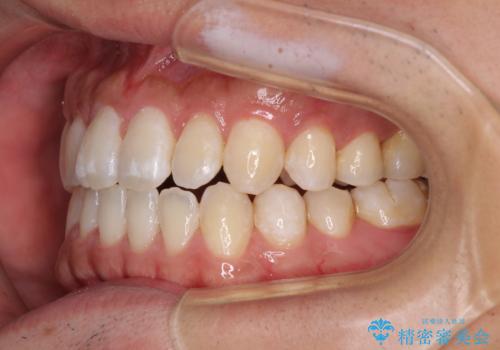

下顎前歯と上顎の部分矯正

- 上下の前歯の叢生を気にして来院された患者様です。

前歯のみの矯正治療を希望でしたが、上顎臼歯が舌側転位していたため、上顎は全体を、下顎は前歯のみを矯正治療することとしました。

矯正治療は上下全顎を行うことが大前提ですが、費用などの点から、今回は部分矯正を選択することとなりました。

患者様本人は咬みにくさを感じていないようですが、部分矯正は咬み合わせの改善が困難であることが多く、咬みにくさが残ることがあります。